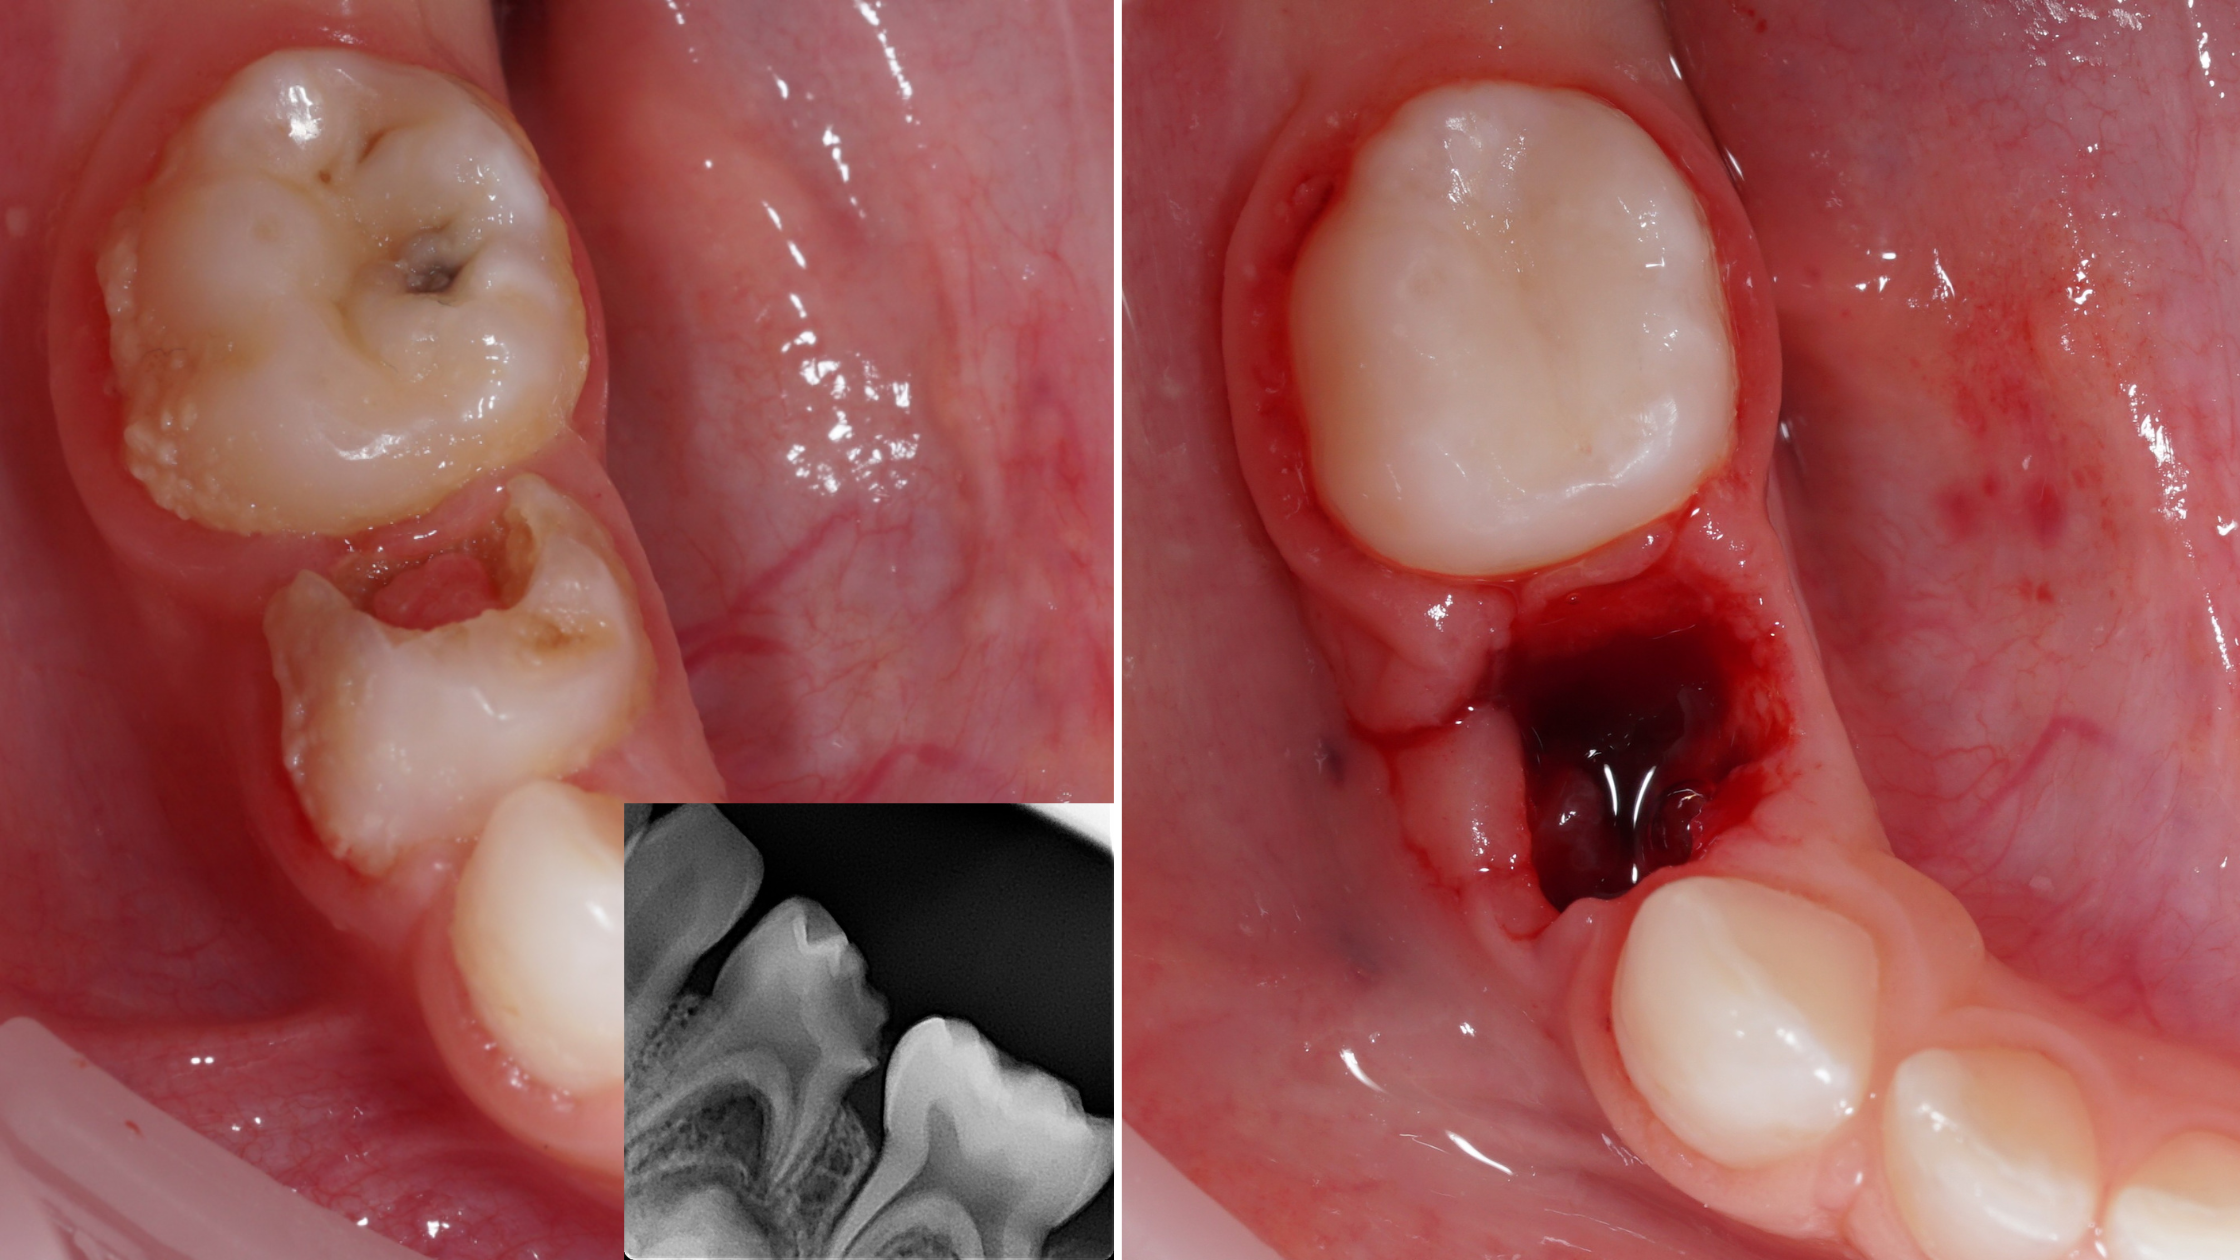

Ekstrakcje zębów mlecznych

• wskazania do ekstrakcji - decyzje graniczne: ratować czy usuwać

• technika znieczulenia miejscowego u dziecka - aspekty anatomiczne i praktyczne

• dobór instrumentarium i atraumatyczne techniki ekstrakcji

• najczęstsze powikłania i sposoby ich unikania

• algorytmy wizyt bólowych: pulpotomia, pulpektomia, ekstrakcja

• analiza przypadków klinicznych: dziecko z bólem, ropień, brak współpracy

• ocena RTG i plan leczenia krok po kroku

• podejmowanie decyzji w sytuacjach niejednoznacznych